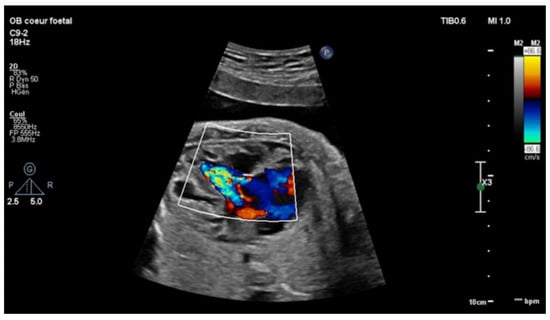

Echocardiography in a fetus at 25 weeks of gestation (WG) from a 19-year-old woman, without history of familial CHD, showed: (i) a typical partial common AVCD with a cleft on the left atrioventricular valve (AVV) without stenosis or leak and a large ostium primum atrial septal defect (ASD); (ii) Ebstein abnormality of the right AVV with a significant leak, causing a dilatation of the right atrium (RA) (Figure 1; Videos S1 and S2); (iii) “functional pulmonary atresia” with inconstant anterograde passage and (iv) retrograde flow in a tortuous ductus arteriosus. Other cardiac structures were normal. Cytogenetic analysis via amniocentesis had normal results. At 30 WG, moderate atrialization of the right ventricle and a pulmonary insufficiency were noted (Figure 2).

Figure 1. Four-chambers view: color Doppler: tricuspid insufficiency from the apex due to Ebstein’s anomaly.